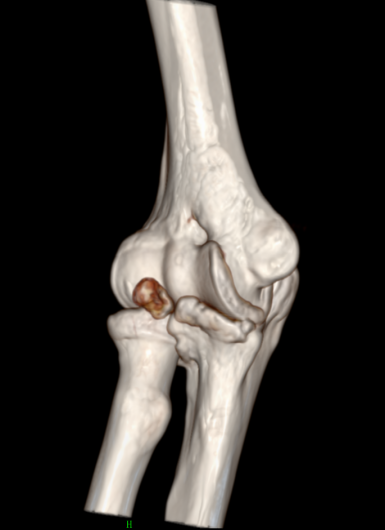

近日,一位52岁的男性患者,因右肘疼痛伴活动受限2周余来pilipili 就诊。经检查,确诊为肘关节骨性关节炎伴游离体。患者于入院第二天在气管插管麻醉下行右肘关节镜探查+滑膜切除+游离体取出术。术后症状明显缓解,疼痛减轻,关节活动范围改善,现已成功出院。

患者鹰嘴骨质增生;前侧关节腔游离体形成

术后CT、DR提示游离体取出